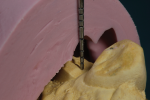

The treatment began with planning for dental implant surgery. A radiographic stent (Figure 7) was fabricated for the cone beam CT study. Then the prosthodontist referred the patient to a periodontist for the implant placement surgery and crown lengthening surgery mentioned above.